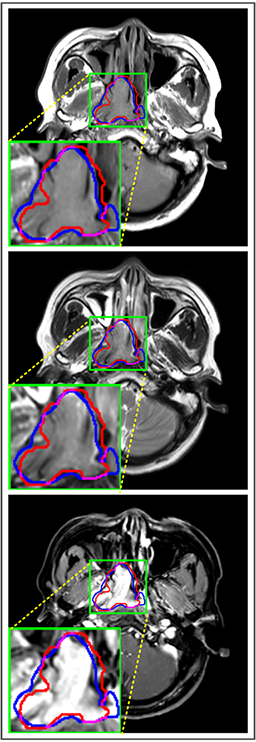

Refer to caption

Figure 9: Predicted results in one single slice image, there are corresponding T1, T2 and CET1 images from top to down. Green regions denote TP𝑇𝑃TP points, red and blue regions denote FP𝐹𝑃FP and FN𝐹𝑁FN point. (a) Ground truth. (b) Patch-based CNN (CET1). (c) Multi-modality patch-based CNN. (d) U-net (CET1). (e) 3D U-net (CET1). (f) Input-level fusion. (g) Merging encoders’ features. (h) MMFNet + multi-MLP + stdPool + self-transfer.

Comparison with related works. Table 1 reports the values of meanDSC𝑚𝑒𝑎𝑛𝐷𝑆𝐶meanDSC, meanASD𝑚𝑒𝑎𝑛𝐴𝑆𝐷meanASD and meanHD𝑚𝑒𝑎𝑛𝐻𝐷meanHD for different methods. Predicted masks of different methods are illustrated in Figure 9 and Figure 10, which respectively present results in 2D and 3D images. Through comprehensively analyzing these results, the proposed MMFNet actually have the following properties:

(i) It directly fuses 3D MRI images rather than 2D slices. Thus, it can effectively use meaningful information from neighboring slices of MRI to realize NPC segmentation. As shown in Table 2, MMFNet can bring 12.26%percent12.2612.26\%, 8.52mm8.52𝑚𝑚8.52mm and 81.19mm81.19𝑚𝑚81.19mm improvements in meanDSC,meanASD𝑚𝑒𝑎𝑛𝐷𝑆𝐶𝑚𝑒𝑎𝑛𝐴𝑆𝐷meanDSC,meanASD and meanHD𝑚𝑒𝑎𝑛𝐻𝐷meanHD compared to the best method based on 2D images (Multi-modality patch-based CNN). And Figure 10 shows that 3D-based methods have less isolated regions (false positives) than 2D-based ones.

(ii) It segments NPC by fusing multi-modality MRIs with the multi-encoder network. Thus, it can learn complementary and interdependent features from different modalities of MRI for final decisions. Additionally, comparing with input-level fusion networks and decision-level fusion networks, layer-level fusion networks (including MMFNet) can effectively capture informative features from different modalities of MRI and fuse low-level features and high-level features.

(iii) It uses a fusion block to fuse low-level features from different modalities of MRI and prepare these low-level features for the fusion with high-level features. Thus, it can more effectively fuse information from various sources. It also uses the self-transfer strategy to initialize the netwerk. Hereby, it can stimulate encoders to make full mining of meaningful features from modality-specific MRI. And it finally improve base multi-encoder-based network (Merging encoders’ fetures) by 2.64%percent2.642.64\%, 1.10mm1.10𝑚𝑚1.10mm and 11.88mm11.88𝑚𝑚11.88mm in meanDSC,meanASD𝑚𝑒𝑎𝑛𝐷𝑆𝐶𝑚𝑒𝑎𝑛𝐴𝑆𝐷meanDSC,meanASD and meanHD𝑚𝑒𝑎𝑛𝐻𝐷meanHD.